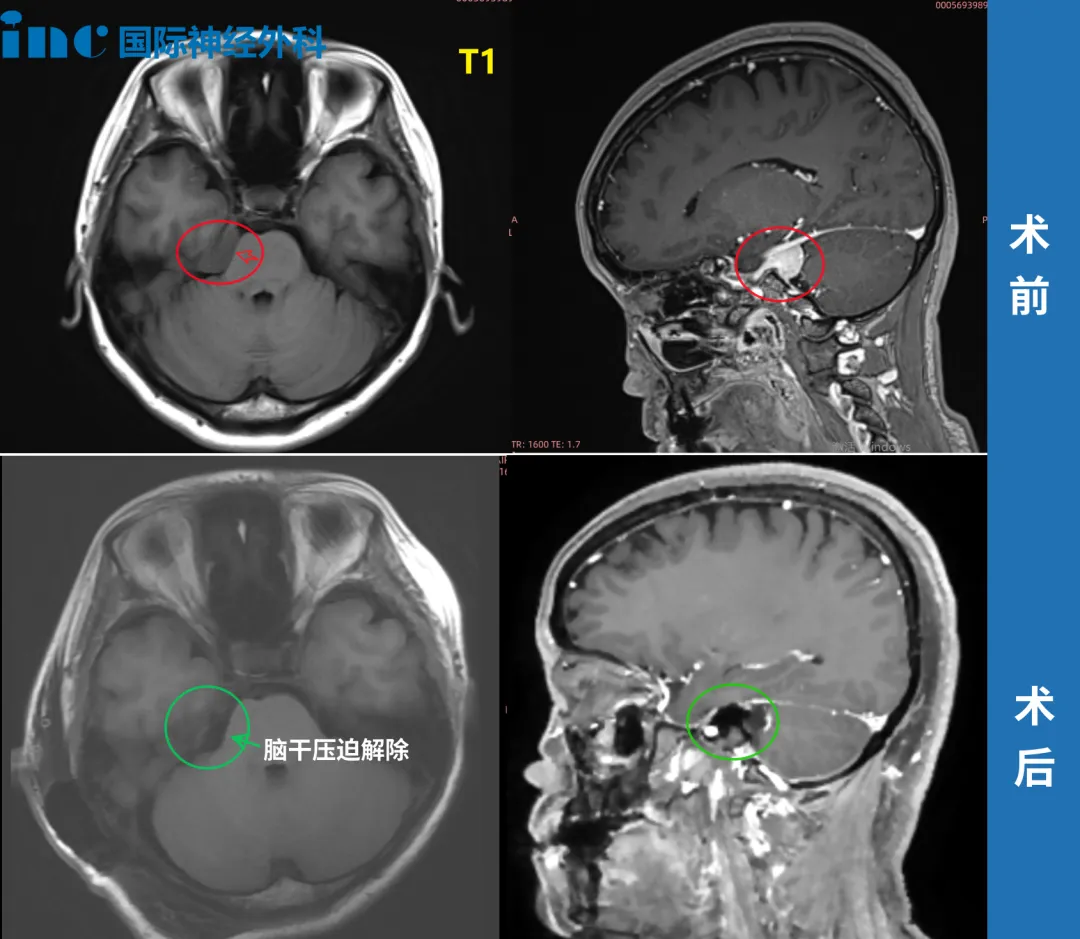

在北京天坛医院,INC福教授为她成功手术——“我在ICU里面呆了4个多小时就出来了,第2天下床,第9天出院。”点击阅读:天坛医院手术纪实|4.5cm脑膜瘤紧压脑干成功手术,勇敢辣妈的彪悍人生!